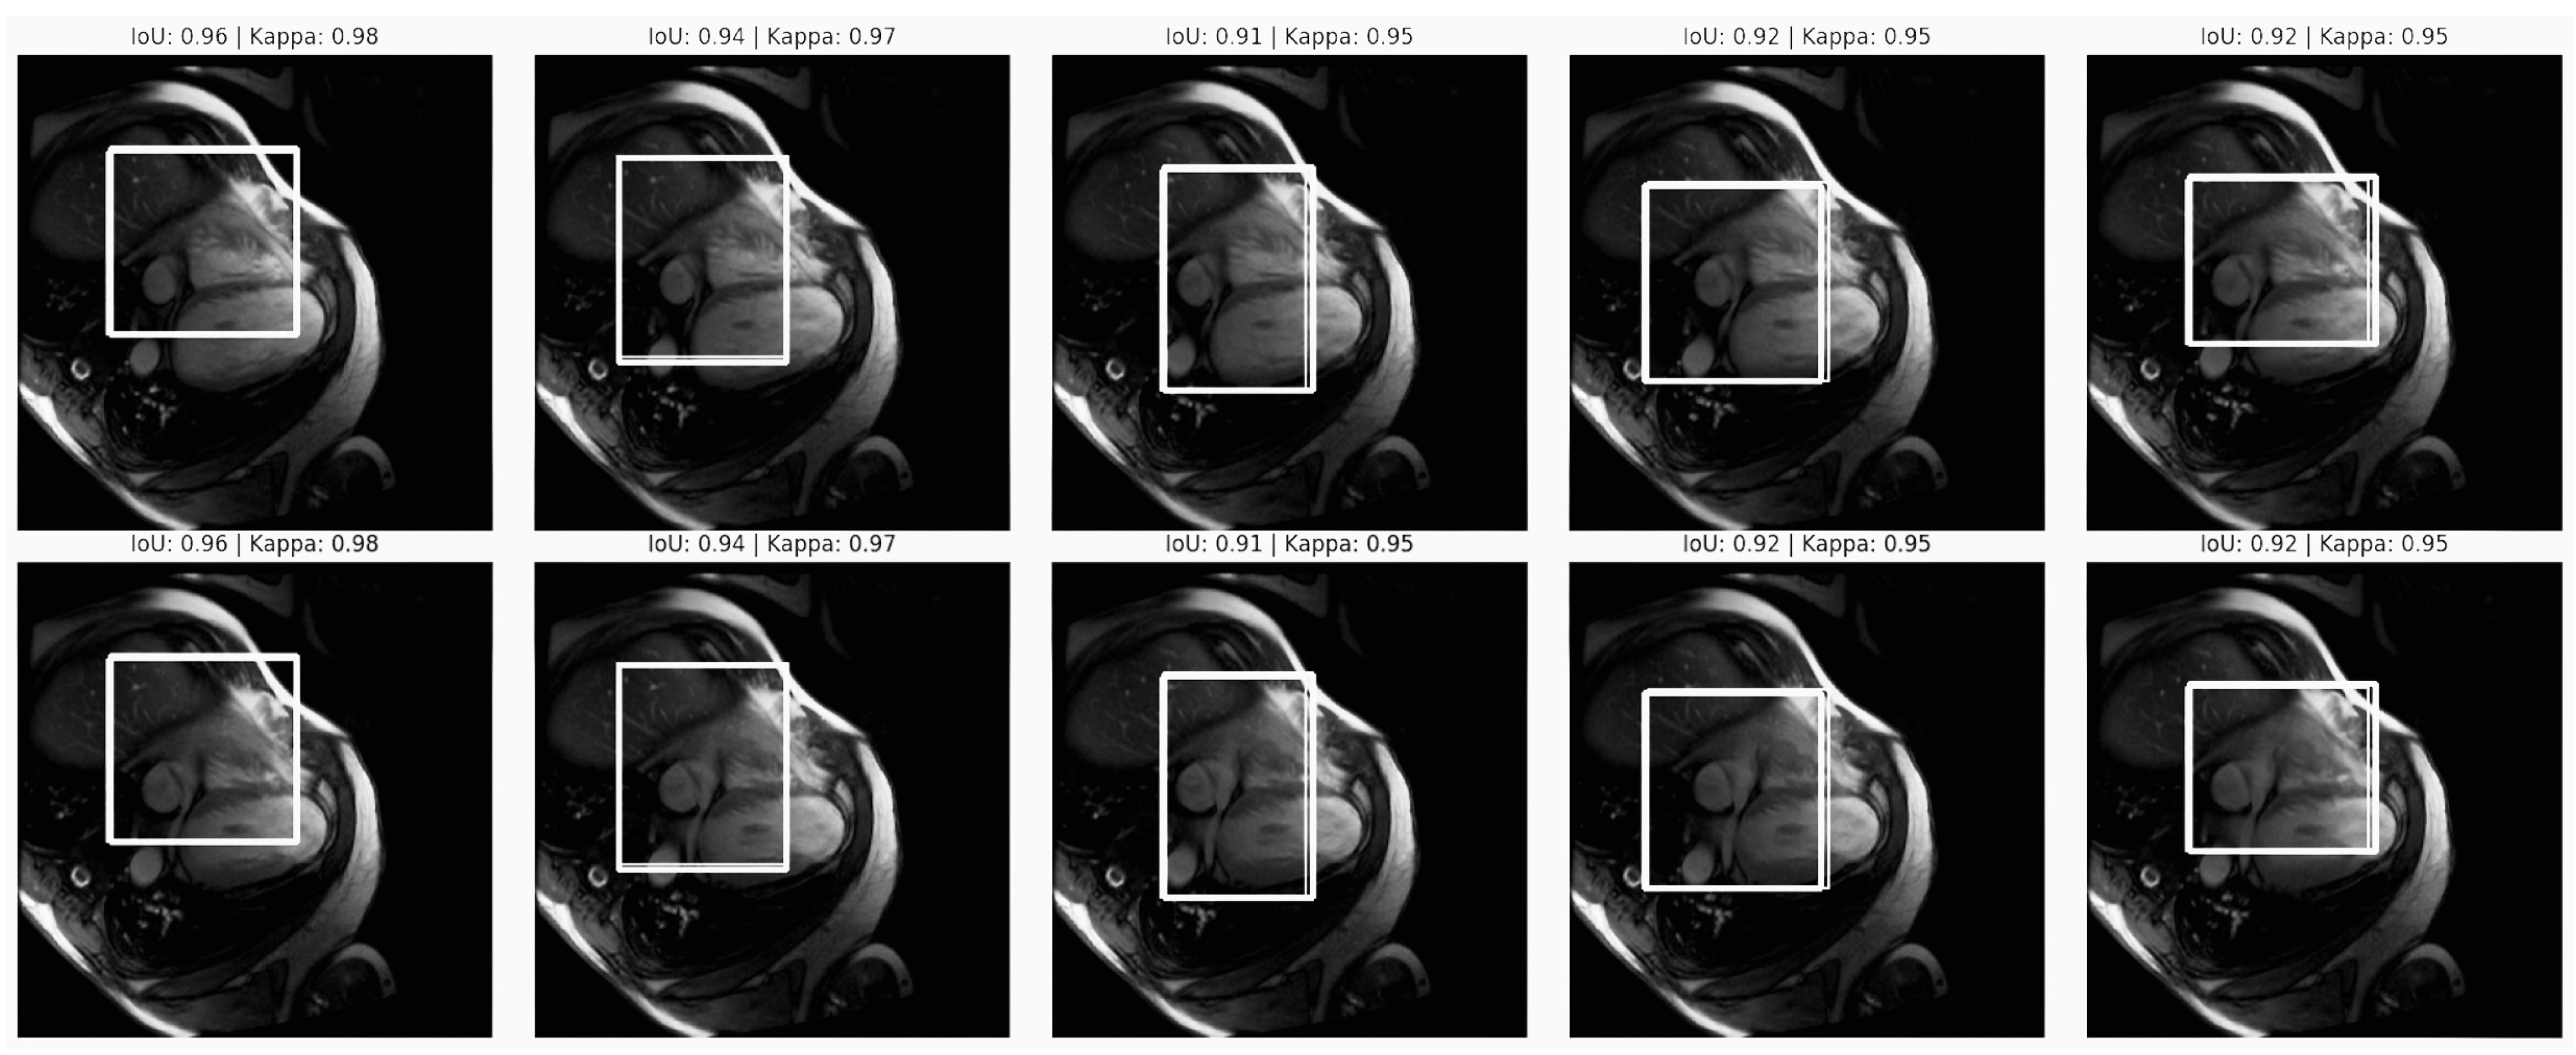

The Intersection over Union (IoU) was determined and a Kappa score analysis was conducted for the purpose of assessing the model reliability in segmenting cardiovascular structures within MRI images. These metrics were chosen to achieve fair and unbiased diagnostics in cardiovascular imaging. By assessing the Intersection of Union (IoU) and Kappa scores, the analysis quantitatively measured how closely the model’s predictions align with ground truth annotations. High IoU values and consistent Kappa scores indicate that the model can accurately identify and segment the heart region across different images. This examination is essential for ensuring that AI-driven diagnostics do not inadvertently introduce variability or bias based on imaging conditions, patient demographics, or anatomical differences. This analysis ensured that the model performed consistently well across various populations to mitigate algorithmic bias, contributing to equitable and accurate cardiovascular diagnostics across patient groups (see the Intersection over Union (IoU) and Kappa score analysis in Figure 10).

The image series shows heart MRI scans with bounding boxes annotated by IoU (0.91 to 0.96) and Kappa values (0.95).

• IoU Values (0.91 to 0.96): These high IoU scores indicate an accurate overlap between the predicted and ground truth bounding boxes, which is essential for precise cardiovascular segmentation. This consistency across images suggests reliable model performance, which is critical for diagnostic applications. Minor IoU variability likely reflects scan quality or anatomical differences, yet it remains within an acceptable range. Ensuring similar IoU across diverse demographic groups would confirm equitable segmentation accuracy.

• Kappa Values (consistently at 0.95): A stable Kappa score reflects that the model has high reliability in segmenting cardiovascular structures due to being able to minimise variations due to imaging conditions. This consistency supports the project’s goal of fair diagnostics as a stable Kappa score across patient subgroups implies reliable, unbiased performance.

The high IoU and consistent Kappa scores affirm the model’s reliability, supporting the project’s equitable AI-driven cardiovascular diagnostics goal. Further validation across diverse populations is necessary to ensure these metrics are generalisable, minimising potential algorithmic bias and promoting fairness in clinical applications.